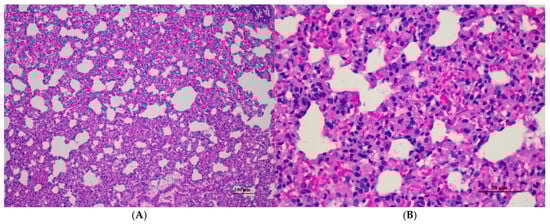

Figure 10.

Histopathological examination of rat lung tissue in sub-acute toxicity from daily (28 days) fed oral dose of CDF showed histopathological alterations. (A) Pulmonary parenchyma reveals prominent thickening of alveolar septa with infiltration of inflammatory cells (100×, H&E). (B) High magnification showed alveolar septa infiltrated by numerous mononuclear cells. Capillary engorgement and focal hemorrhage were observed (400×, H&E).

Figure 5.

Histopathological examination of rat lung tissue in acute toxicity from a single oral dose of CDF exhibited histopathological changes. (A) Lung tissue shows marked alveolar septa thickening with disrupted alveolar structure. Interstitial areas are expanded by cellular infiltrates (100×, H&E). (B) High magnification showed septal infiltration by mononuclear cells, hyperemia, and mild hemorrhage in alveolar space (400×, H&E).

Histopathological analysis revealed generally unremarkable findings in the liver, kidney, heart, and spleen, with only minor, scattered hepatocellular swelling and vacuolation in the liver, mild renal tubular degeneration in limited kidney areas, and focal myocardial vacuolation and lymphoid aggregation in the heart. Conversely, the lung exhibited significant pathological changes, characterized by alveolar septal thickening due to severe interstitial infiltration of lymphocytes and other mononuclear cells, nodular lymphoid aggregations, alveolar septal engorgement and hyperemia, alveolar edema, and multifocal mild alveolar hemorrhage, suggesting a potential site of inflammatory response.

Histopathological analysis of rat organs following 28-day cassava fiber administration revealed mild hepatocellular swelling and vacuolation in the liver, deemed within normal limits, while the kidneys, heart, and spleen exhibited no significant lesions; however, the lungs consistently displayed moderate to severe alveolar edema, septal engorgement, hemorrhage, and inflammatory cell infiltration, suggesting a potential pulmonary response to the cassava fiber, despite the absence of overt clinical toxicity.

Lung abnormalities in the lung tissue of both sexes were found, i.e., interstitial pneumonitis. The histopathologic features of the lungs show varying severity degrees of alveolar edema, alveolar septal engorgement, alveolar hemorrhage, and inflammatory cell infiltration to pulmonary parenchyma. In all groups, this abnormality may indicate infection from laboratory animals. However, further investigation is required. Cassava pulp dietary fiber was found to be well tolerated in a short-term toxicity assessment with non-toxic thresholds of 10.01 g/kg body weight/day for male rats and 11.21 g/kg body weight/day for female rats. Cassava pulp dietary fiber also showed cholesterol-lowering effects [4].

Abnormalities were found in the lung tissue of both sexes, i.e., interstitial pneumonitis. The histopathologic feature of the lungs shows varying severity degrees of alveolar edema, alveolar septal engorgement, alveolar hemorrhage, and inflammatory cell infiltration to pulmonary parenchyma in all groups. Normal lung tissue, except for alveolar septal thickness and alveolar hyperemia, was found in both satellite groups. This abnormality may indicate infection from the facility used for laboratory animals. However, further investigation is required.